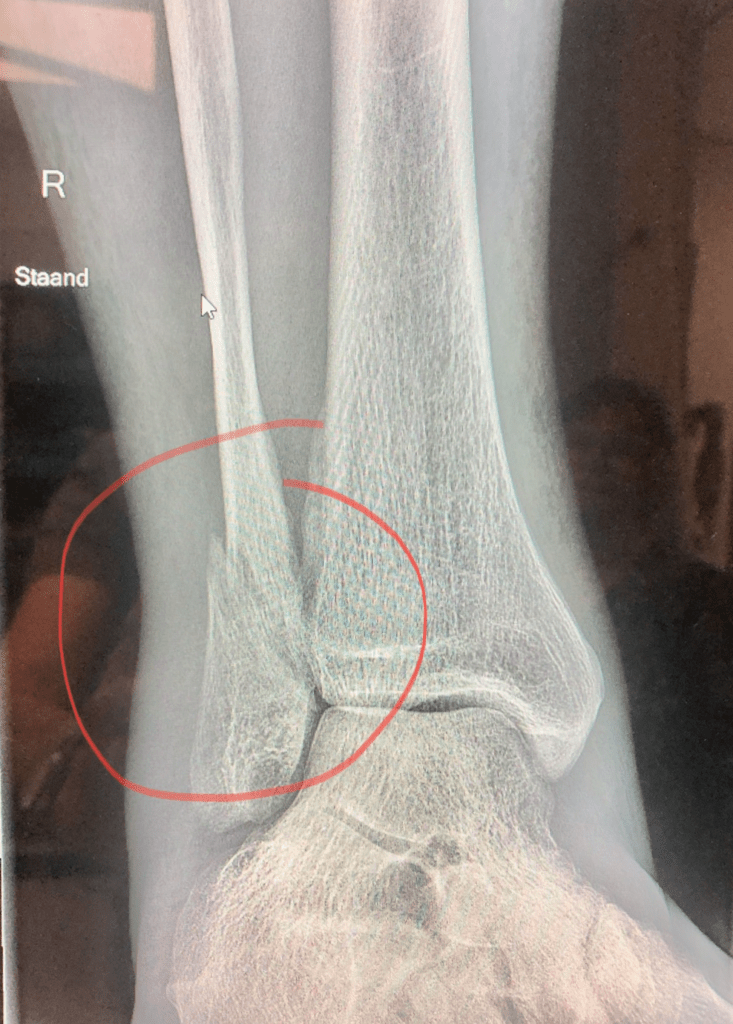

Ap gaat vanmiddag naar het Alrijne Ziekenhuis voor een röntgenfoto van zijn been/enkel en een bezoek aan de poli chirurgie. Hij is bang een forse schrobbering te krijgen maar dat viel mee. Op de foto is te zien dat de breuk “nog niet is geconsolideerd”. Een dergelijke breuk van het kuitbeen heeft wel 6 maanden nodig om te genezen, zei de arts, en die zijn nog niet voorbij. “Heb geduld, meneer Zwinkels!” “U moet nog een tijdje de brace van uw vrouw gaan gebruiken. En stevige schoenen dragen. De breuk moet rust krijgen.”